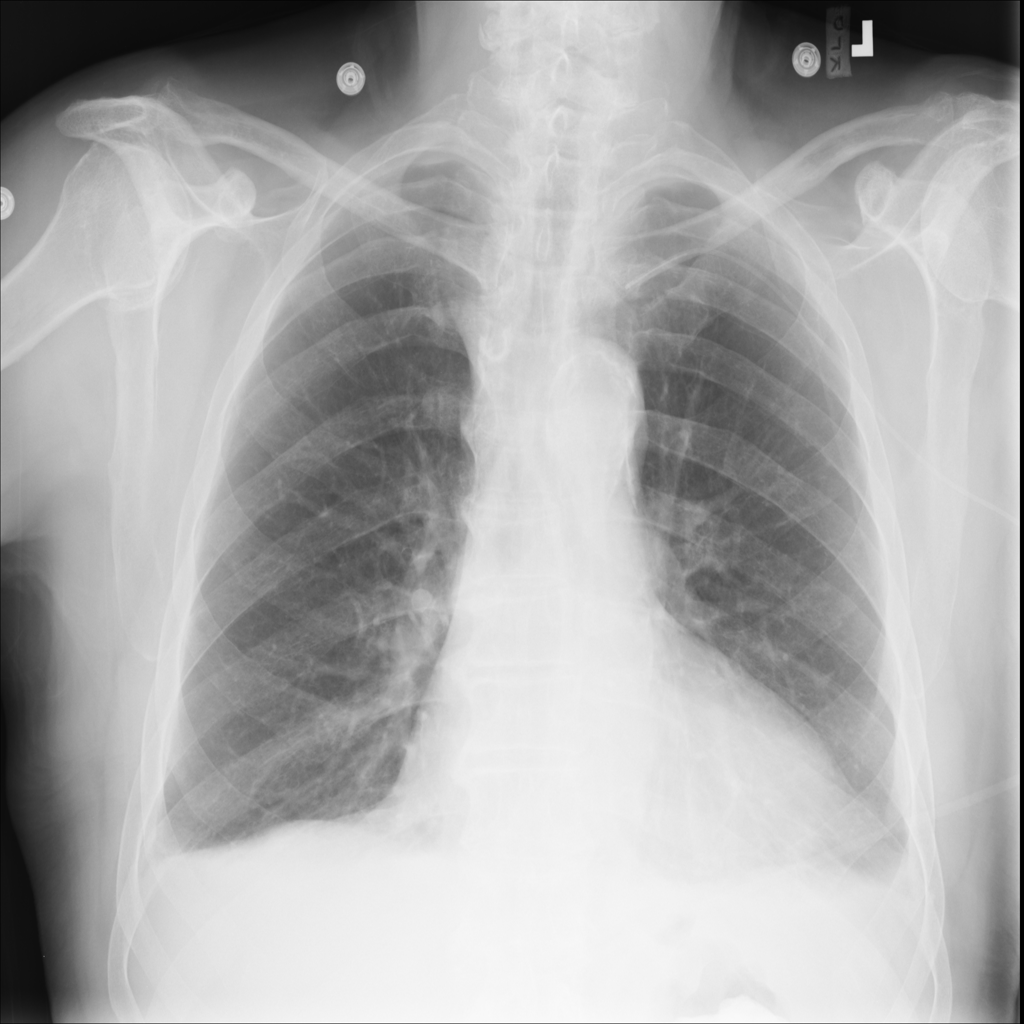

PAT-86C8 · IMG-000Effusion

PAT-86C8 · IMG-000

PA